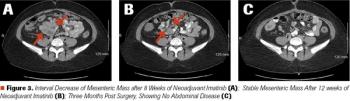

ABSTRACT Gastrointestinal stromal tumors (GISTs) are rare neoplasms of the gastrointestinal tract. They commonly present with nonspecific symptoms and thus are often discovered incidentally. They are best identified by CT scan and most stain positive for CD117 (C-Kit), CD34, and/or DOG-1. Several risk stratification classification systems have been developed based on tumor size, mitotic rate, location, and perforation. Traditional chemotherapy and radiation therapy have been very ineffective, making surgery the mainstay of treatment. The discovery of mutations associated with these tumors has revolutionized the treatment approach. Imatinib mesylate, a selective tyrosine kinase receptor inhibitor, used as adjuvant or neoadjuvant therapy, has greatly improved the morbidity and mortality associated with GISTs. As the survival of patients has increased with the long-term use of targeted therapies, quality-of-life issues now have become much more relevant and have come to the forefront of care. We present a young woman who was successfully treated for GIST but now faces associated long-term adverse effects of imatinib, including the challenge of preserving fertility and the potential for childbearing.